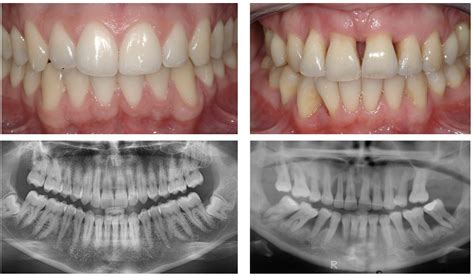

Tooth sensitivity, often described as a sharp pain when exposed to thermal stimuli, can stem from various sources. Enamel erosion, usually due to acidic foods and drinks or aggressive brushing, can lead to dentin exposure. Similarly, gum recession, potentially from aging, poor oral hygiene, or aggressive flossing, exposes the softer dentin layer. Understanding these causes allows for targeted interventions to reduce sensitivity.